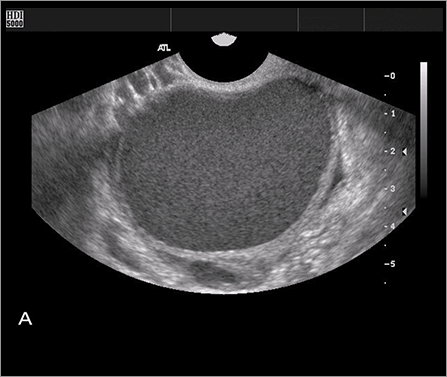

어느 정도 병변이 진행된 중증 자궁내막증은 질초음파나 혈중 CA125 농도를 통해 어느 정도 추정이 가능하나,

확진을 위해서는 복강경을 통환 관찰이 필요합니다.

초기의 자궁내막증은 초음파검사나 CA125측정을 통해서도 정확히 알기 어려운 경우가 많아서

증상 및 상기 검사를 통해 임상적으로 추정합니다.